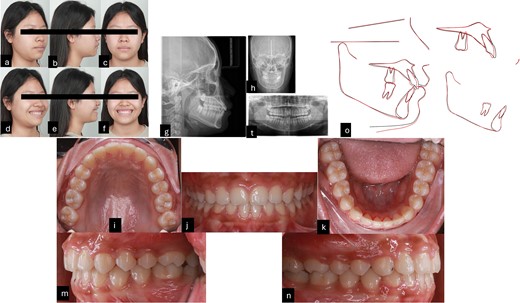

After 16 months of orthodontic treatment, all treatment objectives were successfully accomplished. This resulted in a well-aligned dentition with all spaces closed, leading to enhanced facial aesthetics, and retracted upper incisors. The overbite and overjet were within normal ranges, achieving a Class I occlusion. There was also a visibly reduced GS after treatment. The superimposition and cephalometric analysis table before and after treatment showed significant improvements in profile and incisor inclination, the clear aligner removable appliance was used for retention (Figs 5 and 6, and Table 1). After 2 weeks of periodontal surgery, the patient’s gingival line has healed exceptionally well. It now wraps around the tooth roots in a scalloped shape, with no black triangles or exposed tooth roots. The surgery also fixed the patient’s GS, resulting in an ideal gingival exposure. As a result, the crowns of the teeth are more visible and stable up to 3 months (Fig. 7).

Post-treatment records. (a–f) Extra oral pictures post-treatment; (g–t) post-treatment radiographies; o: superimposition before and after treatment; (i–n) intraoral pictures post-treatment.